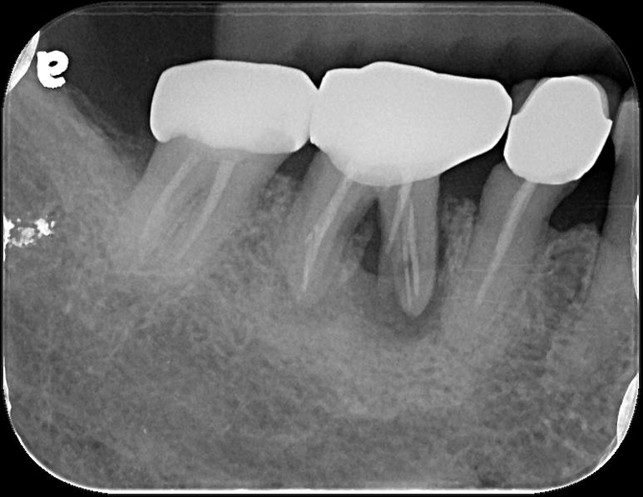

治療後根尖片